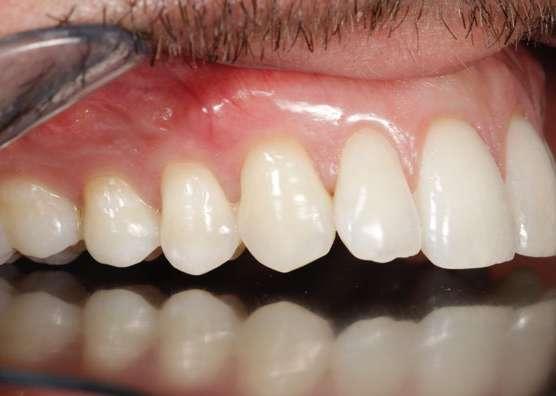

OPCIONES TERAPÉUTICAS

EN EL MANEJO PERIODONTAL Y ORTODÓNCICO DE CANINOS INCLUIDOS MAXILARES

Este artículo de revisión evalúa el manejo de la impactación de los caninos permanentes maxilares. Esta alteración presenta una etiología multifactorial y es la impactación más frecuente después de la de los terceros molares. Para llevar a cabo un correcto tratamiento es necesario un exhaustivo estudio clínico y radiográfico. El tratamiento de los caninos incluidos es ortodóncico-quirúrgico y se realiza en tres fases: ortodoncia prequirúrgica, cirugía de acceso al canino y ortodoncia posquirúrgica.

La impactación de los caninos permanentes superiores es la segunda forma más común de impactación de dientes después de los terceros molares, siendo dos veces más común en mujeres que en hombres (Becker y cols. 2015). La erupción del canino permanente suele ocurrir alrededor de los 11 años, por lo que la sospecha de su inclusión suele comenzar a los 14-15 años. La impactación palatina es más frecuente que la impactación vestibular (3 veces) y la unilateral más común que la bilateral (Chung y cols. 2011). La etiología es multifactorial y podría estar relacionada, entre otras causas, con discrepancias en el tamaño del diente y la longitud de arcada, genética, erupción tardía, deficiencia transversal del maxilar, migración dentaria, traumatismo en el maxilar o agenesia/anomalía de posición en incisivo lateral (Martínez Madero y cols. 2022; McConnell y cols. 1996).

Clínicamente, los caninos incluidos se caracterizan por la erupción retardada del canino permanente, la erupción asimétrica de ambos caninos, la ausencia de protuberancia canina en el fondo de vestíbulo o presencia de protuberancia palatina en la región canina, el retraso en la erupción o migración distal de incisivos laterales permanentes, la retención prolongada de canino temporal sin movilidad y pérdida de vitalidad o el aumento de movilidad de incisivos permanentes (Mason y cols. 2001).

de tracción favorable del 1.3 y desfavorable del

Ericson y Kurol en relación a: ángulo alfa, posición mesio-distal, altura del canino respecto al LAC del lateral y grado de erupción del canino.

Actualmente, la tomografía computarizada de haz cónico (CBCT por sus siglas en inglés: Cone Beam Computed Tomography) y la reconstrucción 3D nos permiten ver con más claridad la posición del canino y su relación con estructuras adyacentes (Alqerban y cols. 2009). En el año 2000 se desarrolló un nuevo método para evaluar, a partir del CBCT, la dificultad prevista para posicionar un canino incluido, el índice KPG. Este índice clasifica la posición del canino en función de su distancia de la norma, dando un número en una escala de 0 a 5 tanto para la

Mariano Sanz

Figura 1. Diagnóstico clínico y radiográfico de un caso de inclusión de caninos. a) Cementado de brackets; b) Corte coronal del CBCT: inclusión por palatino de 1.3 y 2.3; c) Arcada con espacio preparado para caninos mediante coils abiertos; d) Radiografía panorámica: pronóstico

2.3 según

artículo de revisión

cúspide como para la punta de la raíz. La suma de las seis puntuaciones obtenidas evalúa la dificultad prevista del canino (Dalessandri y cols. 2013).

En relación con el tratamiento de este tipo de inclusiones dentarias, la literatura refiere que la extracción del canino temporal como tratamiento interceptivo es beneficiosa para la erupción espontánea del canino incluido, siempre y cuando tenga una posición y distancia favorables respecto al plano oclusal (Ahlam y cols. 2023; Almasoud 2017; Benson y cols. 2021). Debido a la etiología mencionada, es necesario conseguir espacio suficiente para favorecer la erupción del canino retenido en aquellos casos que no lo tenga, con aparatología fija multibrackets o alineadores. En otros casos, la expansión rápida del maxilar y la posterior colocación de una barra transpalatina, seguidas de la extracción del canino deciduo, son opciones de tratamiento interceptivo eficaces para pacientes de 9 a 13 años que presentan caninos palatalmente desplazados (Baccetti y cols. 2011).